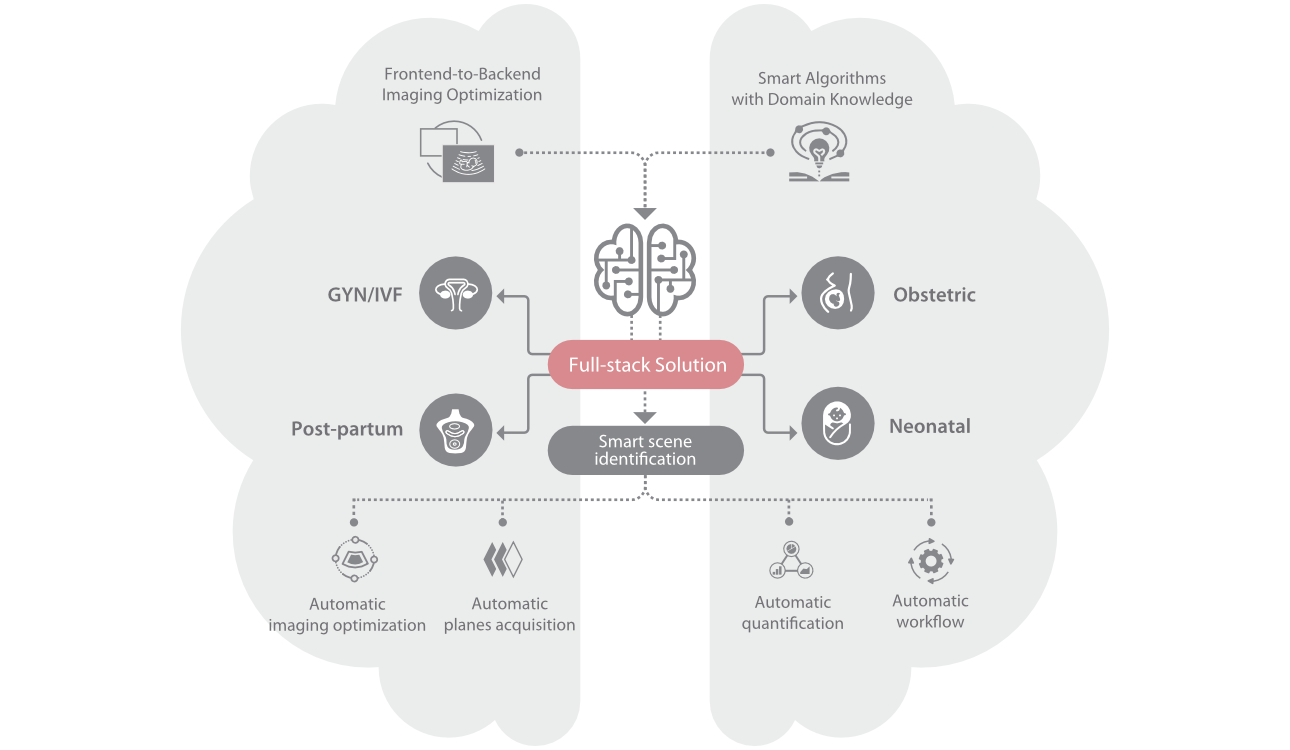

Nuewa I9? ??? ???? ?? ??? ?? ??? ???? ?? ??? ???? ???? ??? ?????. ??? ??? ??? ?? ????? ?? ???? ???? ???? ???? ??? ???? ??? ??? ???? ??? ???? ??? ?? ?????.